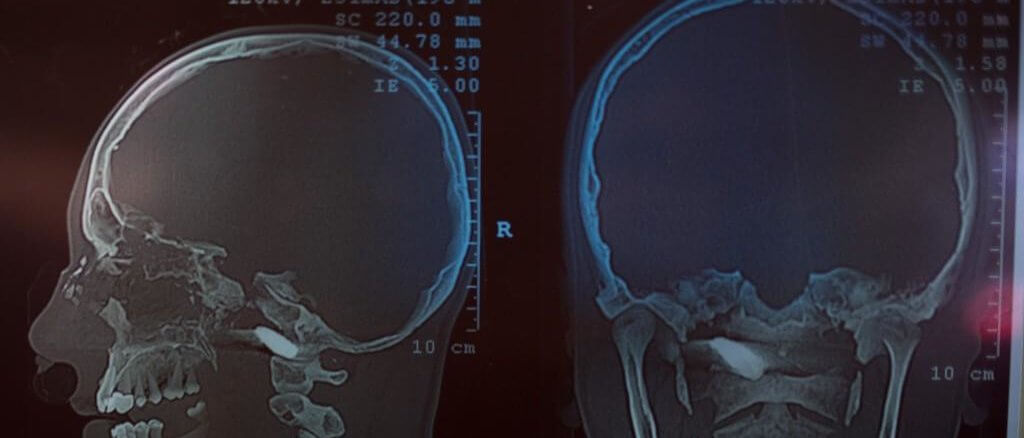

CONFIDENCIAL tiene en su poder 19 tomografías realizadas en el Lenin Fonseca, de las cuales 15 corresponden a pacientes heridos con armas de fuego en la cabeza. Al menos ocho de ellos fallecieron, según los médicos consultados. Sus identidades han sido confirmadas por este medio de comunicación y el Centro Nicaragüense de Derechos Humanos (Cenidh).

Las tomografías revelan disparos precisos en las frentes, parietales, temporales y occipitales de las víctimas. Otros en las regiones cervicales y del tórax. Cráneos estallados, desplazamientos de la línea media cerebral, inflamaciones y hemorragias graves. Salvarse de esas lesiones es muy difícil.

Los impactos de bala presentan en su mayoría orificios de entrada y salida, trayectorias que dejan una estela de destrucción en la masa cerebral. En las tomografías, pueden verse como un surco gris abierto por el proyectil que deja, en algunos, esquirlas de plomo o de hueso desperdigadas. Balas poderosas.

“Jefferson Flores Medrano. 25 años. Trayectoria de la bala de arriba hacia abajo. Entró frontal y salió parietal occipital. Herida tangencial de una bala de alto poder, porque fracturó en múltiples pedazos el cráneo a lo largo de la trayectoria. Un estallamiento craneal”, detalla el doctor mientras analiza las tomografías. El daño óseo puede observarse mejor cuando el médico ordena al software mostrar la tomografía en 3D: Cráneos astillados, resquebrajados, pómulos dinamitados…

El doctor no puede determinar el proyectil que asesinó a Flores Medrano, porque no está. Traspasó la cabeza, pero no duda que es una bala de fusil como en la mayoría de las víctimas. En el caso de José Alfredo Leiva fue disparo de AK-47; y en el de Nesker Velázquez, escopeta. En el de Kevin Dávila López, se trata de un balín circular de 1.85 centímetros de diámetro.

“Es un orificio circular. Esta munición no se encuentra en ninguna armería. Es un balín especial de uso exclusivo de fuerzas policiales. La esfera metálica entró en la región fronto-temporal derecha y quedó alojado en la región fronto-parietal izquierdo”, dictamina el experto. El balín puede verse alojado en el cerebro. Al ser un proyectil de menor potencia, el doctor cree que el disparo fue ejecutado a una distancia no tan alejada.

La tomografía de Darwin Medrano, realizada el 22 de abril a las 10:42 de la noche en el Lenin Fonseca, revela una trayectoria de bala de arriba hacia abajo. Entró por la nariz y terminó en la base izquierda del cráneo, muy parecido al caso de Rivas Martínez, en Masaya.

Ante la falta de autopsias a las víctimas de la represión por parte del Estado, las tomografías del Lenin Fonseca aportan información valiosa para el esclarecimiento de los crímenes.

La tomografía de Urroz Jirón en poder de CONFIDENCIAL muestra una de las ejecuciones de disparo más letales entre las víctimas. Con exactitud el proyectil entró en la línea media del cráneo, vía parieto-occipital, y al salir por la frente estalló todo el hueso. “No se salvaba nunca de ese disparo. Eso es una bala de alto poder, porque no quedó en la cabeza. Balas de ese calibre solo las tiene la Policía”, insiste el experto en balística.

Eliecer Aguirre Centeno fue asesinado en Sébaco el 14 de mayo, después de que Monseñor Rolando Álvarez sacara la procesión del Santísimo. El disparo le fracturó totalmente el cráneo, como puede apreciarse en la tomografía.